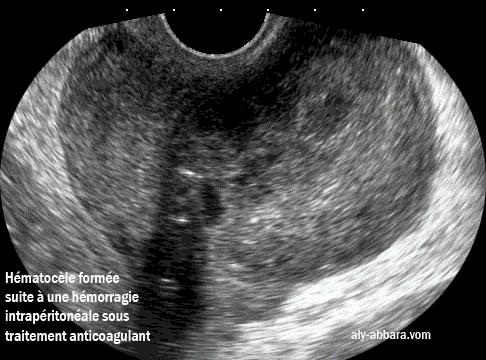

Hematocèle ou uh hématome organisé dans le cul-de-sac postérieur (de Douglas)